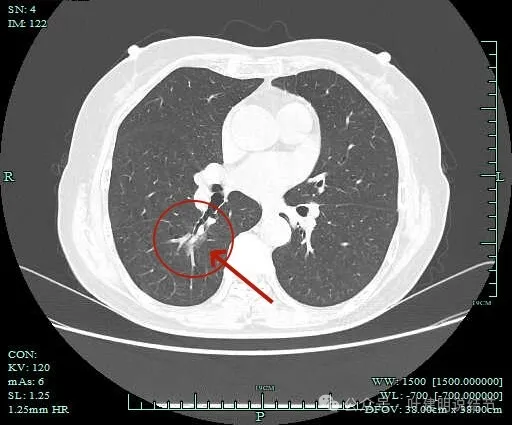

病灶出现,淡磨玻璃密度,但轮廓较清,且表面不平。

病灶内部有走行的支气管,但显得有些僵硬;病灶表面有浅分叶。